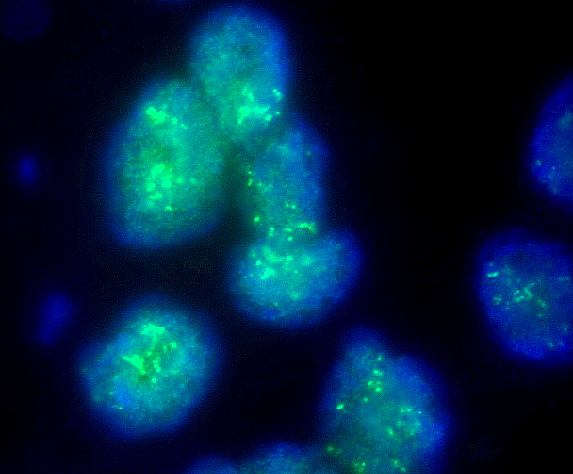

Molecular / cytogenetics images